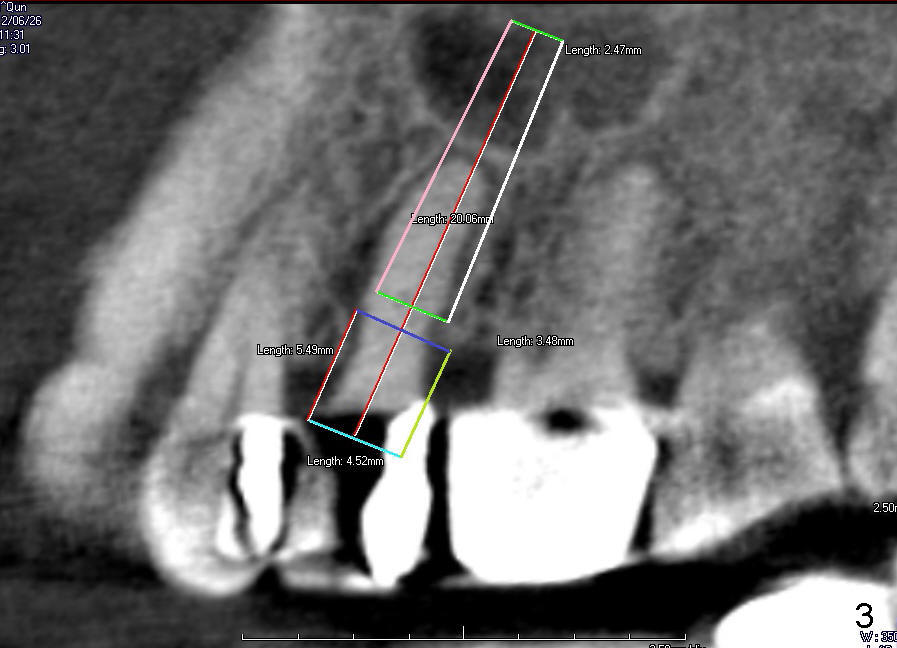

The tooth #13 has broken down to residual root now. CBCT sagittal (Fig.1,3) and coronal (Fig.2,4) sections show designs of T (4.5x17 mm Fig.1,2) and D2 (Fig.3,4) implants. Which is better? It appears that sinus lift with bone graft is expected.

In fact, D2 implant is placed.